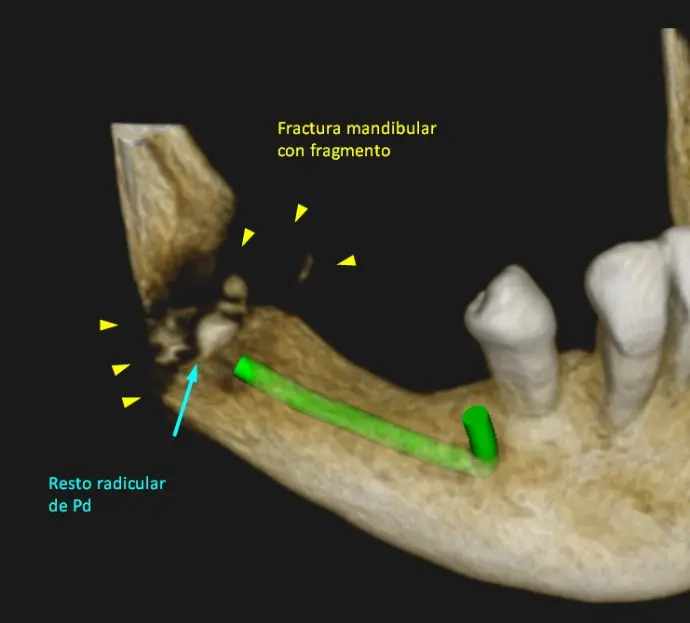

Tanto en la radiografía panorámica (imagen 1) como la tomografía maxilar inferior se puede observar una fractura mandibular a la altura del Angulo de la mandíbula con resto de fragmento óseo. (Fx Conminutas) Como también se logra ver todavía resto radicular de pieza dentaria. Ver imágenes 2 a imagen 5.

Para mayor información detallada se procedió a realizar una tomografía Cone Beam que abarque mas la zona de interés: zona Rama y Angulo de la mandíbula. Ver imágenes 6 a imagen 9.